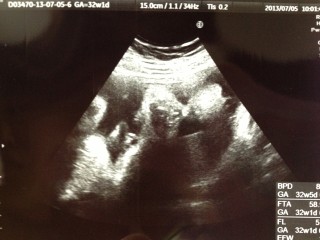

前回30Wの健診エコーでブチャイクに写った我が娘。今回はエコープラスコンデジで動画撮影。かわいく写って一安心(ToT) ただ…BPD8.6(35W相当)AC27.5(33W相当)FLは31W相当と、頭と胴体はデカく足は短いというタラちゃんのような体型にお育ちになっているようだ…できれば足が長くなってほしいワガママ親心。 推定体重は1964gでした。 母体体重は妊娠前+2.9kgでいい感じだけど足の浮腫みと今回初めて尿蛋白が出てしまった。対策は大概やり尽くしているからこれで悪化して管理入院になったらどうしようとまた別な心配事ができてしまった。